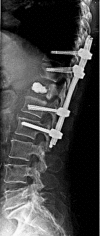

Percutaneous minimally invasive versus open spine surgery in the treatment of fractures of the thoracolumbar junction: a comparative effectiveness review

Objective: To determine the comparative effectiveness and safety of percutaneous minimally invasive versus open spine surgery for fractures of the thoracolumbar junction.

Results: • Two studies (Level of Evidence III) met our inclusion criteria. • Radiographic outcomes were similar between treatment groups. • Postoperative incisional pain was less in patients undergoing percutaneous MIS. • Patient function as assessed by the Hannover Spine Score, the SF-36 and the MacNab criteria were slightly higher in the percutaneous minimally invasive group, but not statistically significant. • Percutaneous MIS resulted in less blood loss and shorter length of hospital stay than open surgery. • No complications were reported using percutaneous MIS.

Conclusion: Limited data suggest that percutaneous techniques are associated with less postoperative pain, less blood loss, a shorter hospital stay, and a slightly better functional outcome. However, concerns remain on the effectiveness of percutaneous techniques in correcting spinal deformity and achieving bony fusion. Further studies are needed to verify these preliminary findings.